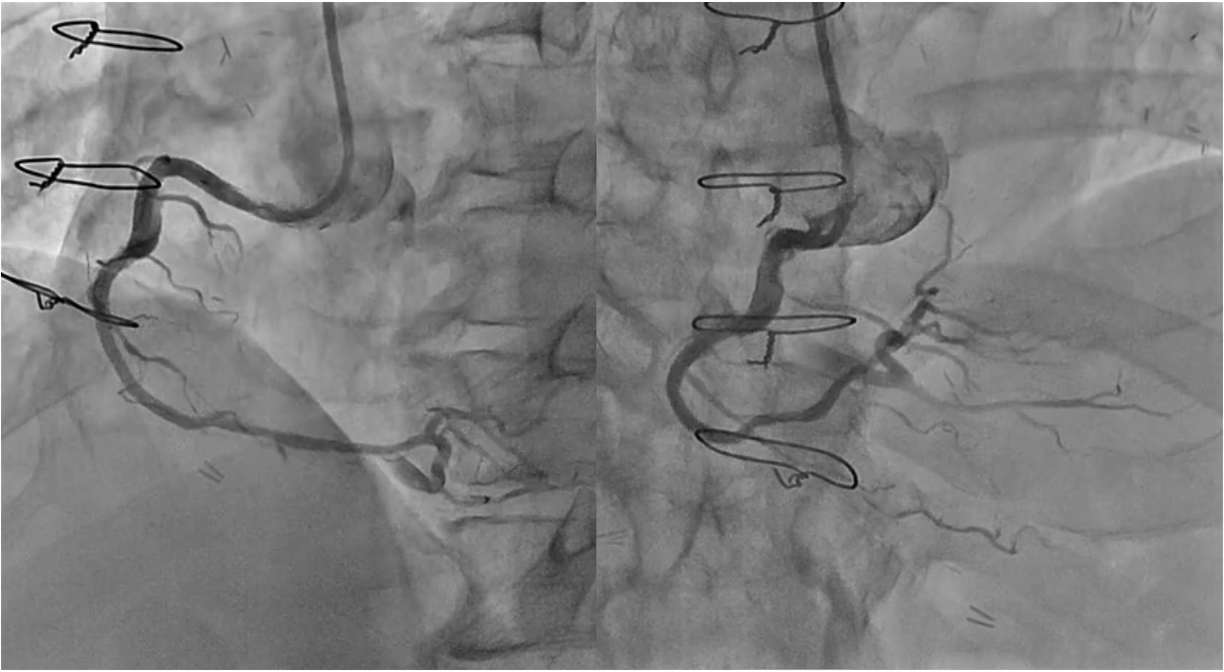

PCI for the degenerated SVG was determined to be at high risk of distal embolism so we planned to perform PCI for native RCA. Antegrade wire crossing was thought to be difficult (J-CTO score was 3 : calcification, bending and lesion length), therefore we planned retrograde approach via SVG. To avoid ischemia during the retrograde procedure, we dilated the severe stenotic lesion in SVG with small balloon and then micro catheter was advanced. It was very difficult to pass the graft anastomosis, but reverse wire technique at distal RCA was effective. Even after the advancement of both antegrade and retrograde wires, it was also difficult to pass the CTO lesion due to strong bending. Finally, retrograde wire was passed with Reverse CART technique and externalization was achieved. After DES implantation, native RCA was nicely revascularized.

Case Summary